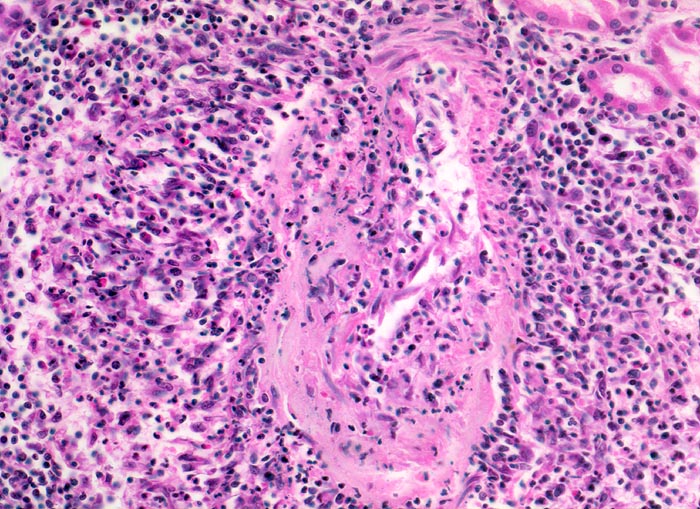

Polyarteritis nodosa Makroform: akute Phase

Mittelgrosse Arterie mit einer nicht ganz frischen fast zirkulären Gefässwandnekrose. Nur ein kleiner Gefässwandabschnitt lässt noch eine Muskelschicht erkennen. Entsprechend der fast zirkulären Nekrose ist das ganze Gefäss mantelförmig umgeben von einem gemischten Entzündungsinfiltrat (neutrophile und eosinophile Granulozyten, Lymphozyten, Plasmazellen und Histiozyten). Stellenweise greift das Entzündungsinfiltrat auch auf die Gefässwand über.

Makroskopischer Befund der Nieren: Vergrösserte Nieren mit Petechien und mehreren frischen, teils hämorrhagischen Infarkten.

Seit einigen Wochen Fieber unklarer Ätiologie, Gewichtsverlust und Anämie. Im Rahmen der Abklärungen erstmals festgestellte arterielle Hypertonie. Der Patient verstirbt an einem Myokardinfarkt.